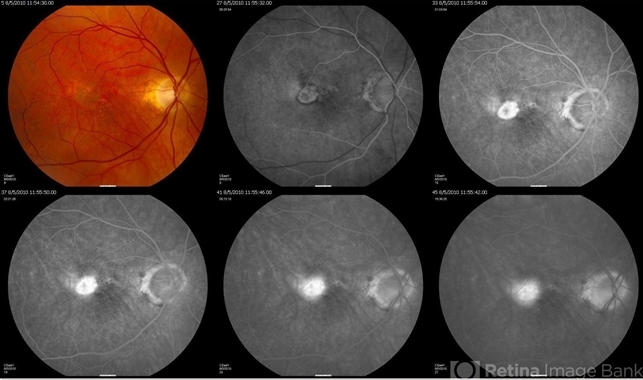

- choroidal neovascularization (CNV), classic form

- Classic CNV.